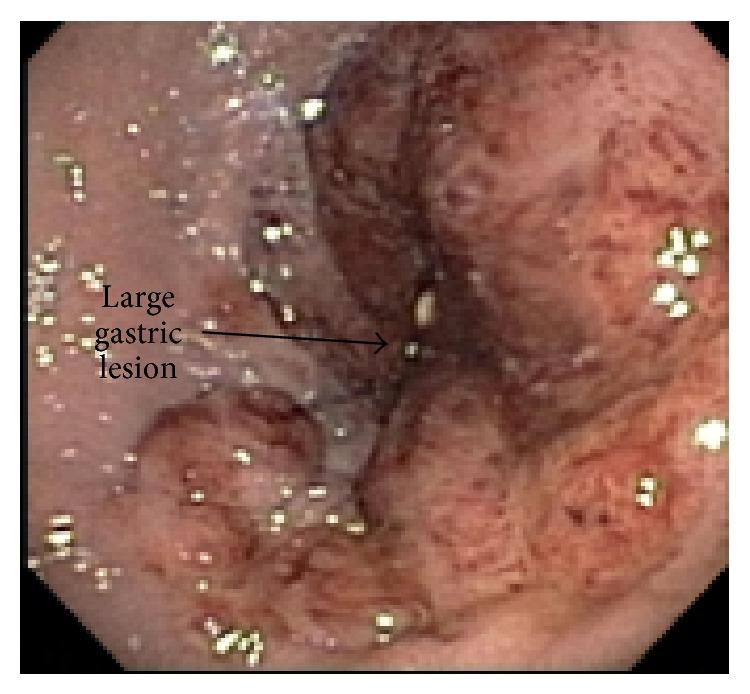

Since the advent of highly active antiretroviral therapy (HAART), the incidence of acquired immunodeficiency syndrome- (AIDS-) related Kaposi's sarcoma (KS) has decreased dramatically. While cutaneous KS is the most common and well-known manifestation, knowledge of alternative sites such as the gastrointestinal (GI) tract is important. GI-KS is particularly dangerous because of its potential for serious complications including perforation, obstruction, or bleeding. We report a rare case of GI-KS presenting as upper GI bleeding in a human immunodeficiency virus- (HIV-) infected transgendered individual. Prompt diagnosis and early initiation of therapy are the cornerstones for management of this potentially severe disease.

自从高效抗逆转录病毒疗法(HAART)问世以来,获得性免疫缺陷综合征(AIDS)相关的卡波西肉瘤(KS)的发病率已大幅下降。虽然皮肤KS是最常见且广为人知的表现形式,但了解胃肠道(GI)等其他部位的情况也很重要。GI-KS特别危险,因为它有可能引发严重并发症,包括穿孔、梗阻或出血。我们报告了一例罕见的GI-KS病例,该病例表现为一名感染人类免疫缺陷病毒(HIV)的变性者出现上消化道出血。及时诊断和早期开始治疗是管理这种潜在严重疾病的基石。